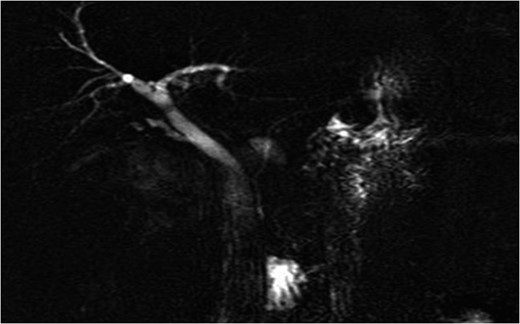

Fluid resuscitation and IV antibiotics were commenced, and an abdominal ultrasound performed. It revealed the presence of a large heterogenous right renal mass. Further evaluation was performed with magnetic resonance cholangiopancreatography. Findings were of a 5.7 × 4.6 cm2 exophytic mass of high T1 signal intensity arising from the posterior right kidney. Adjacent to the mass was a large 8.3 × 10 cm2 retroperitoneal haematoma (Fig. 1). These findings were consistent with a ruptured angiomyolipoma. The adjacent common bile duct was dilated at 8 mm, secondary to mass effect (Fig. 2).

Admission imaging revealing dilatation of the common bile duct (8 mm), due to external compression.